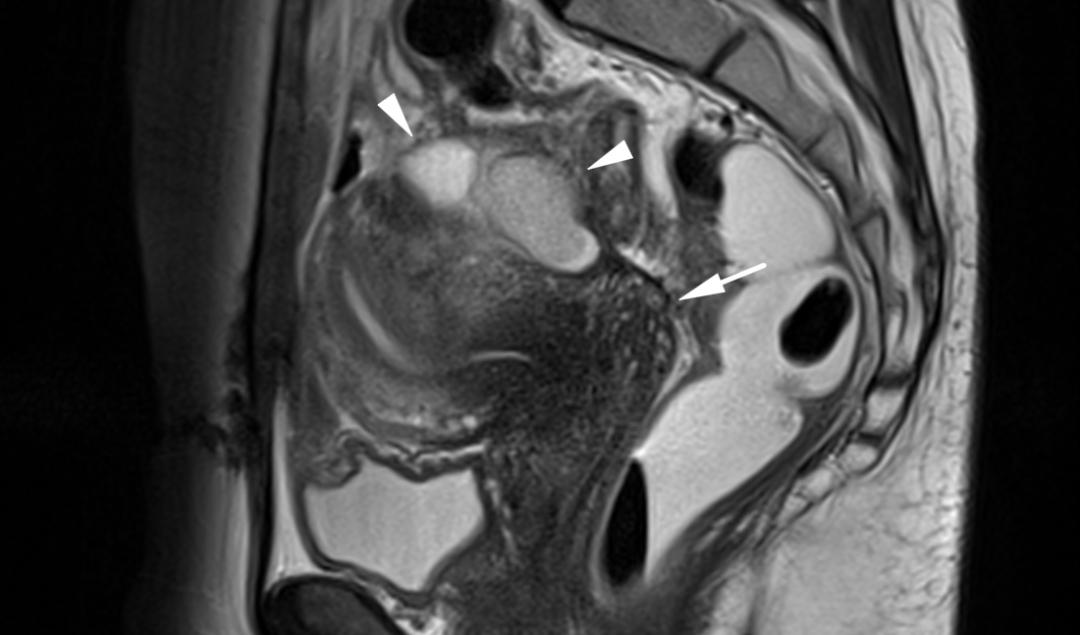

子宫内膜异位至右侧卵巢,T2WI 矢状位呈类圆形高信号,注意的是同时异位至道格拉斯窝及宫颈后区,T2WI 矢状位显示病灶呈低信号,中间夹杂更高信号结节,T1WI 轴位显示病灶多发高信号结节(提示多发出血点)